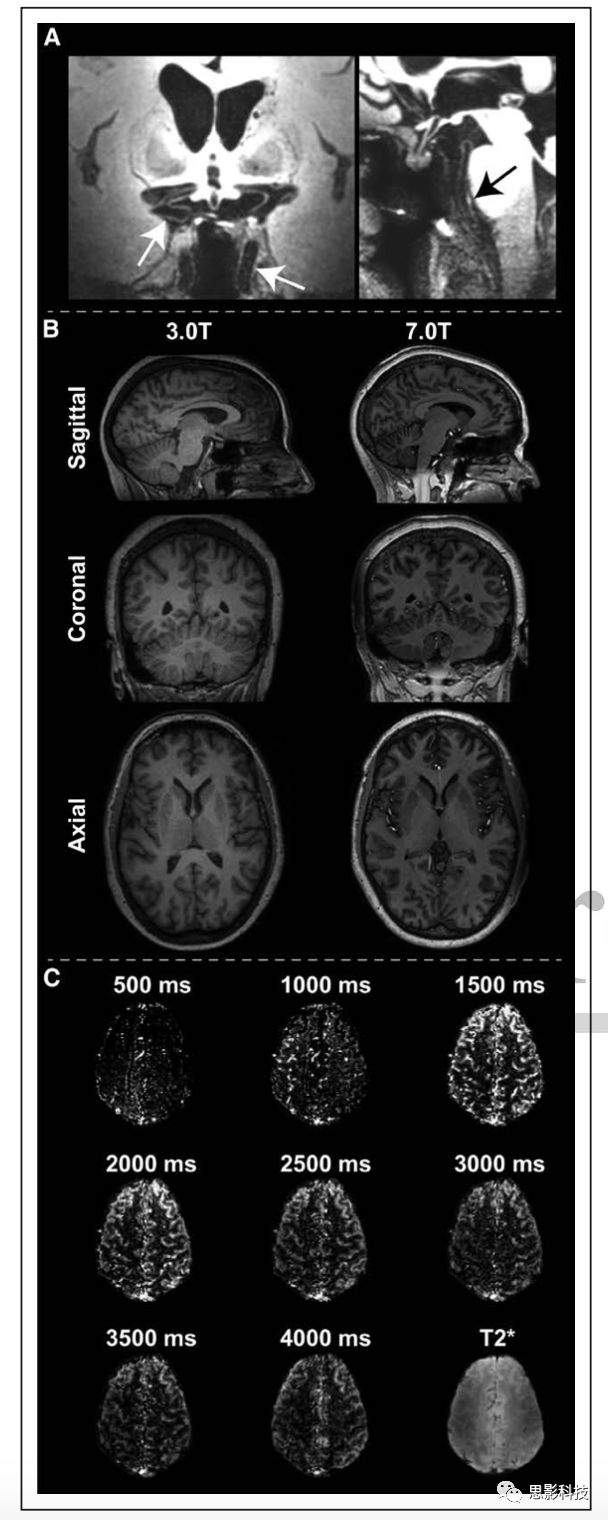

1動脈自旋標記磁共振成像(ASL-MRI)監(jiān)測外科血管重建。A:在ASL-MRI中,使用單個(脈沖或連續(xù)的)或一系列(偽連續(xù)的)射頻脈沖對血液進行磁性標記,之后反轉(zhuǎn)的血液流入成像層面的毛細血管,與組織液交換,并衰減血管外水信號。通過將該圖像與其中未標記血液的圖像進行比較,可以獲得灌注加權(quán)圖。B:煙霧病合并左側(cè)頸內(nèi)動脈床突上段閉塞、右側(cè)頸內(nèi)動脈遠端局灶性狹窄和雙側(cè)大腦中動脈閉塞患者的飛行時間磁共振血管成像。

C:雙側(cè)腦硬膜動脈貼敷術前后(左后22個月,右后16個月)ASL-MRI顯示術后腦血流量(CBF)改善情況。FLAIR:流體衰減反轉(zhuǎn)恢復。

越來越多的兒童使用ASL-MRI測量組織水平的CBF(圖1),可一致地顯示大腦中、前動脈區(qū)域的低灌注模式,且常伴有后灌注。煙霧病的ASL結(jié)果非常復雜,因為血液到達時間很長,根據(jù)成像參數(shù)的不同,可以表現(xiàn)為沒有信號或高信號。當CMRO2的影響可忽略或發(fā)生微小變化時,CBF增加,毛細血管和靜脈內(nèi)和周圍順磁性脫氧血紅蛋白相對于抗磁性氧合血紅蛋白的比例將減少,從而延長周圍水T2和T2*,增加MRI信號(即血氧水平依賴[BOLD]效應)。因此,T2*加權(quán)序列可用于在影響血液和組織中二氧化碳和pH水平的代謝時進行腦血管反應性繪圖:使用藥物誘導的碳酸酐酶抑制劑(如乙酰唑胺)或呼吸刺激(如高碳酸血癥)。腦血管反應性可能比基礎CBF更能預測預后,因為它表明組織實質(zhì)對灌注壓力變化作出反應的能力。該方法已應用于兒童煙霧病血管病變。

現(xiàn)使用的磁共振大多數(shù)為1.5T-3.0T,然而,美國食品和藥物管理局(FDA)最近批準了將7.0T磁共振投入臨床使用,這可能為下一個十年提供新的研究方向。信噪比隨磁場強度線性增加,因此,理論上,達到3T掃描的相同空間分辨率,7.0T用不到一半的時間即可完成。這對解剖結(jié)構(gòu)較小且時間依從性有問題的未用鎮(zhèn)靜劑的兒科病例很有幫助。且7T還有額外優(yōu)點,在3T磁共振中化學交換飽和轉(zhuǎn)移、BOLD和ASL等方法存在的問題,如化學位移離散度的增加,血管內(nèi)相對于血管外的液體T2*信號降低,血液T1值延長,在7T中會得到改善(圖4)。在實踐中,優(yōu)點也包括高空間分辨率,精確定位BOLD中功能區(qū)域,允許ASL更長的標記延遲時間。但7.0T的也存在很多技術難題,包括所需的發(fā)射場不能保證在目前安全范圍內(nèi)獲得,主磁場和發(fā)射場的不均勻性,植入物發(fā)熱問題,有限的線圈覆蓋范圍問題以及7.0T系統(tǒng)的可訪問性有限。7.0T磁共振成像臨床相關應用的綜述。doi: 10.1016/j.ejrad.2011.07.007

4高場解剖像和血流動力學成像。A 7.0T血管壁成像顯示顱內(nèi)血管壁節(jié)段(白色箭頭)和基底動脈病變(黑色箭頭)。B同一志愿者在3.0T(1mm)和7.0T(0.7 mm)條件下,常規(guī)掃描時間為5min,進行T1WI掃描。C 7.0T,不同的標記后延遲時間的ASL圖像,展現(xiàn)了長到達時間(3000-4000ms)定量腦血流量的潛力,這在中風中比較常見。圖來自一名成年人。